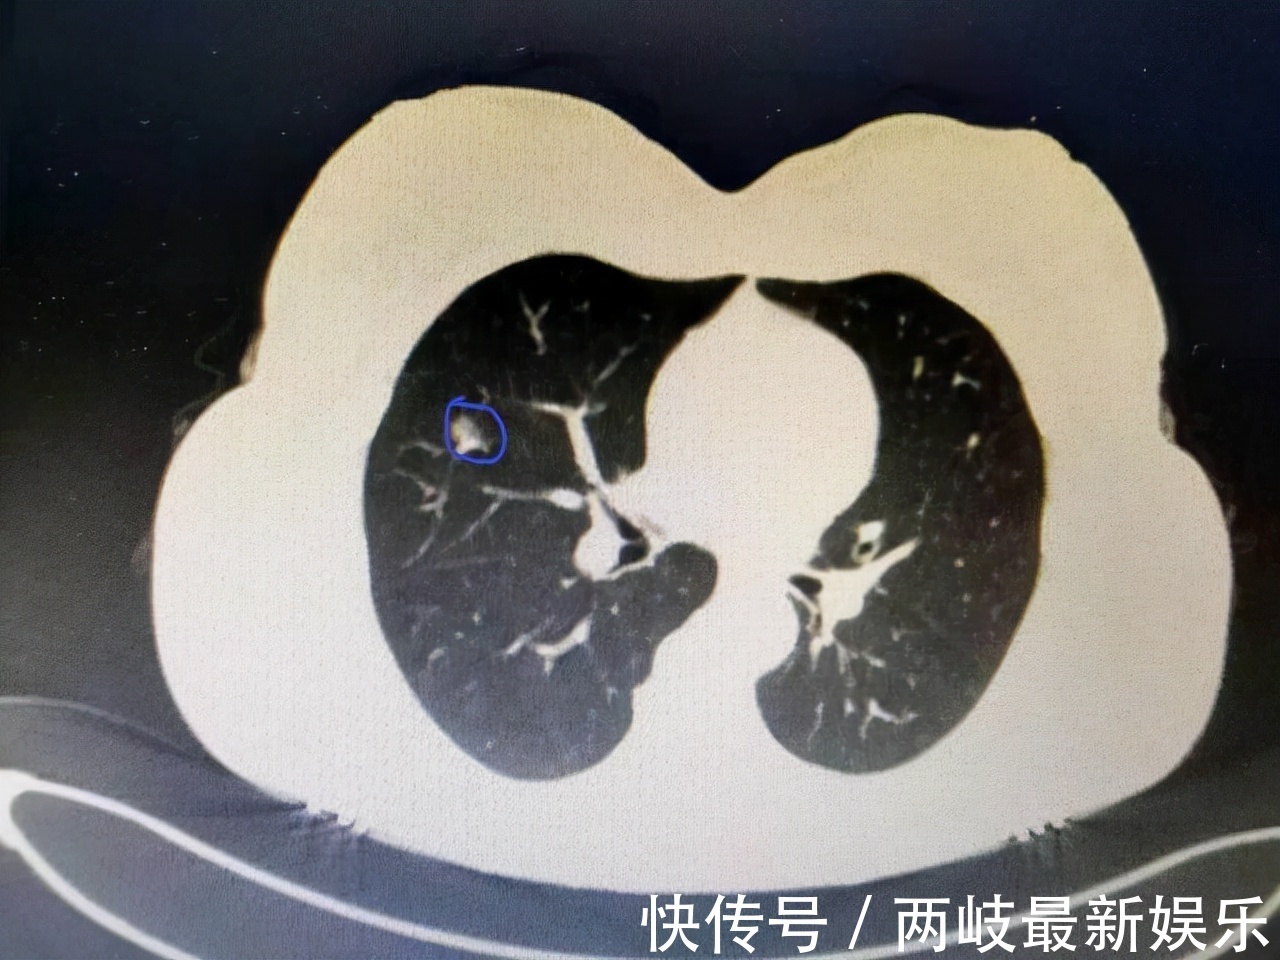

文章插图